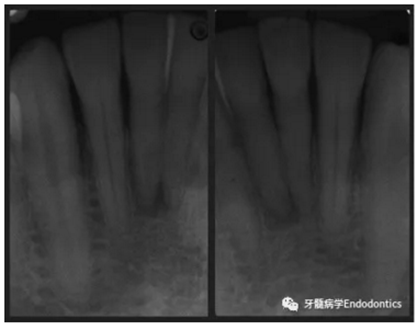

31、41叩痛明顯,牙冠變色(圖1)。溫度和牙髓電活力測(cè)試無反應(yīng)。兩張從不同角度拍攝的x線片顯示,相對(duì)于側(cè)切牙,雙側(cè)下中切牙都有嚴(yán)重的根管鈣化(圖2)。41有明顯根尖周暗影,31根尖周暗影不明顯。為進(jìn)一步證實(shí)31是否存在根尖周病變,同時(shí)精細(xì)觀察31、41的復(fù)雜結(jié)構(gòu),根據(jù)歐洲牙髓病學(xué)會(huì)CBCT應(yīng)用指南(2014),對(duì)患牙拍攝小視野、高分辨率CBCT。CBCT影像證實(shí)31、41均伴有根尖周炎和嚴(yán)重的根管鈣化(圖3)。距離根尖4mm可見根管影像。 由于患牙根管解剖結(jié)構(gòu)較為復(fù)雜,筆者決定使用特殊設(shè)計(jì)的微型鉆頭(直徑0.85mm)進(jìn)行“數(shù)字化導(dǎo)航牙髓治療”。 因此對(duì)下頜進(jìn)行口內(nèi)掃描(圖4)。用coDiagnostixTM軟件(Dental Wings Inc.,Montreal,Canada)將CBCT和口內(nèi)掃描的數(shù)據(jù)進(jìn)行處理,該軟件主要用于引導(dǎo)種植。通過該軟件對(duì)兩個(gè)掃描圖像進(jìn)行疊加后,虛擬鉆頭尖端沿牙長(zhǎng)軸對(duì)準(zhǔn)根管下段可見部分(圖5)。三維檢查虛擬鉆的正確位置。

圖2. 31、41X線影像。

圖3.下頜前牙CBCT影像。